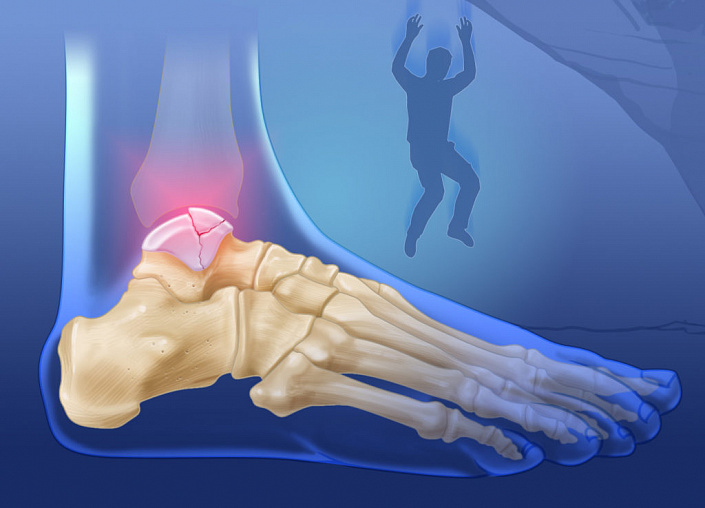

Переломы костей стопы лечатся долго, так как кости многочисленны, мелки и близко расположены, а стопа подвержена нагрузкам. Определить место перелома довольно проблематично, так как болевые ощущения могут распространяться не только на само место перелома. О переломах свода стопы, где кости неподвижны и прочно скреплены связками, человек может и не подозревать, так как боль не так ярко выражена. Чаще ломают плюсневые кости и ладьевидную кость, когда роняют что-то тяжёлое на стопу.

Выделяют также усталостный перелом пяточной кости, когда эта кость испытывает слишком большие нагрузки, имеется анатомический дефект или дегенеративные заболевания костей. Встречаются у спортсменов или военных, вынужденных передвигаться на большие расстояния с дополнительным весом.

Пальцевые фаланги (особенно у мизинца) ломаются тоже часто, но зато срастаются быстрее всего. Медленнее всего восстанавливается таранная кость, она находится большей частью внутри, не имеет достаточно хорошего кровоснабжения и принимает на себя вес тела. Травмировать таранную кость в быту сложно, но можно при серьёзных авариях, в которых, как правило, травмируется вся стопа.